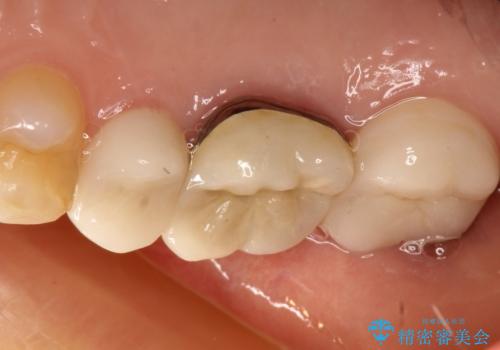

- 右上の奥歯がしみるとのことで確認すると、右上の一番奥の歯の銀歯の下が虫歯になっていました。

かなり大きな銀歯が装着されていたので、かぶせ物にて治療を行うこととなりました。

同時に右上の後ろから3番目の歯のかぶせ物も適合が悪かったので同時に治療することとなりました。